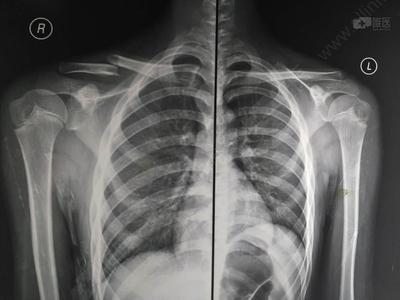

锁骨骨折有鼓包图片

锁骨骨折有鼓包图片,锁骨错位重叠长好图片

男12岁,锁骨骨折保守还是手术

锁骨错位重叠长好图片

锁骨完全错位畸形愈合

锁骨骨折错位愈合图片

锁骨骨折图片